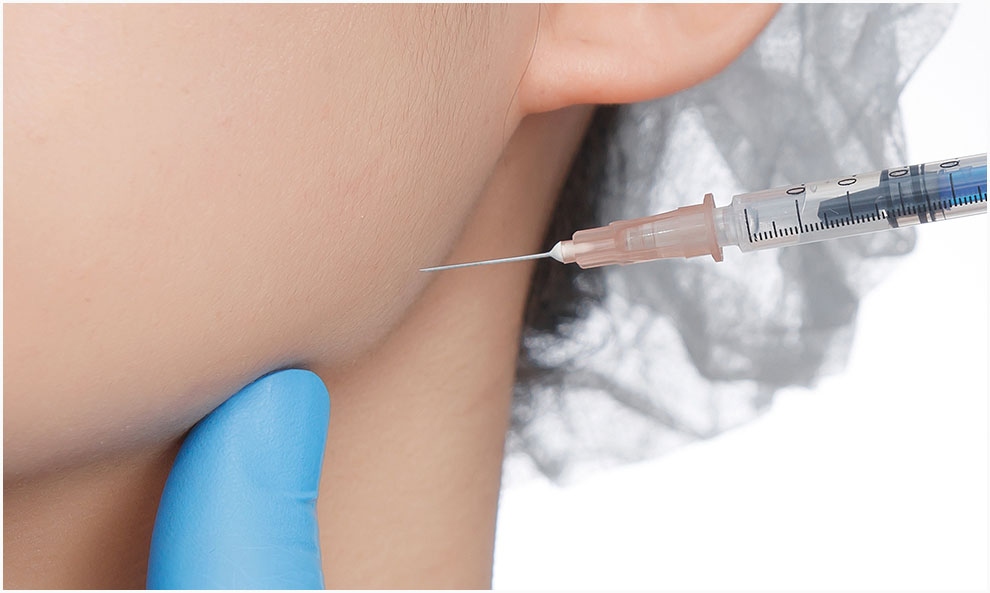

보톡스, 고주파 등 비침습적 치료를 통하여 단기적이나마 통증 개선 효과를 볼 수 있습니다.

턱관절에 생긴 문제로 인하여 과도한 턱 근육으로 이어지기도 하는데 이러한 상황에서 인대에 자극을 주며 개선하는 것입니다.

수술에 비하면 적은 비용으로 치료가 가능하겠지만 근본적인 문제 해결에는 부족한 방법입니다.